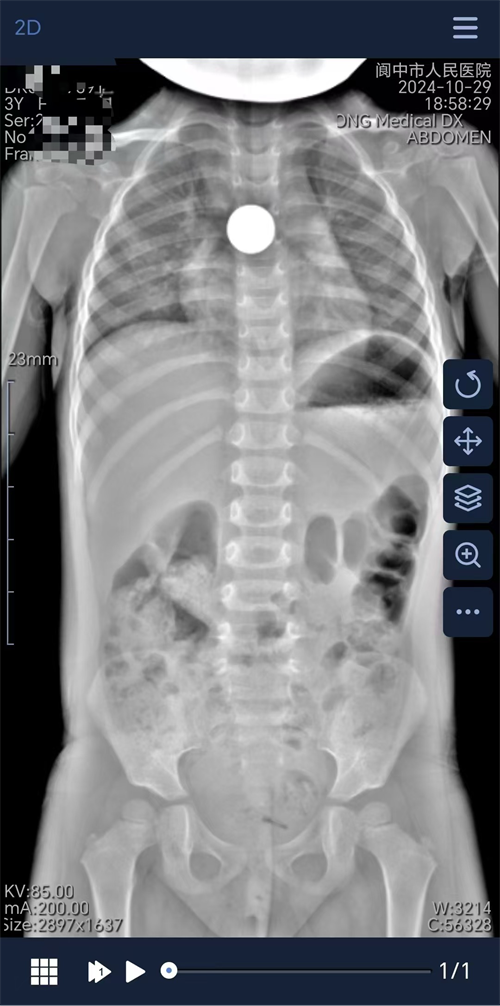

近日,一名年仅3岁的女童在玩耍过程中不慎将一枚硬币吞入腹中,家长紧急将其送至阆中市人民医院就医。

经紧急腹部X片检查,在患儿食管内发现硬币,异物卡顿位置处于中纵隔区(约平胸5、6层面)。鉴于小儿食管狭窄且异物较大,若不及时取出,会致使患儿局部食管黏膜缺血坏死。消化内科值班医生与家长充分沟通后,决定立即采用无痛胃镜取出硬币。